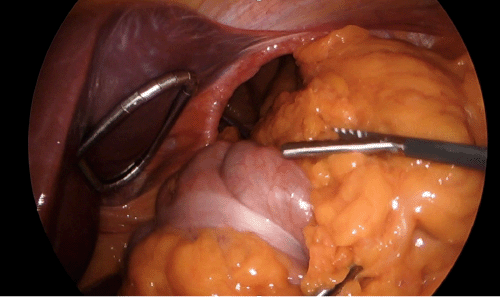

The patient subsequently underwent a laparoscopic paraesophageal hernia repair. Intraoperatively, the hiatal defect was noted to be significantly enlarged. Reduction of the herniated viscera commenced with careful mobilization and retrieval of the small bowel from the mediastinum (Figure 2). The greater omentum and transverse colon also required extensive mediastinal dissection before complete reduction into the abdominal cavity could be achieved. The stomach was found to be densely tethered within the mediastinum, necessitating division of the short gastric vessels to facilitate its full reduction. Following extensive blunt and electrocautery dissection, the stomach was successfully repositioned intra-abdominally, and both diaphragmatic crura were clearly visualized (Figure 3).

Figure 3. Intraoperative Visualization of the Diaphragmatic Defect Post-Reduction. Published with Permission

The image provides a clear and full visualization of the large diaphragmatic defect (hiatus) prior to surgical repair